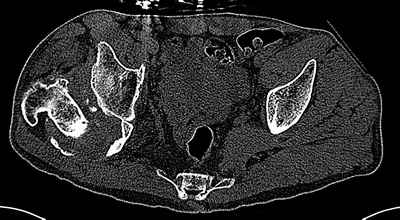

На последнем срезе КТ задний край практически отсутсвует по сравнения со здоровой стороной. Разумеется, что это плоскостное изображение, но головка вывихнулась не только в плоскостную щель захваченную на КТ. Если вы считаете, что удастся установить туда чашку даже низкопрофильную, остается пожелать вам успехов. Но перед этим можно смоделировать установку чашки на скиаграммах КТ.

За пожелание успехов - спасибо, думаю это пригодится, не очень понял про плоскостную щель, специально предоставил срезы на уровне свода - он цел, дефект заднего края ниже, за счет заглубления он будет еще меньше, по данным 3d - должно получиться.

Решение по ВВ придется принимать по месту.... Сумеете "подрыться" и получить хорошее покрытие чашки (+2 винта об-но) - хорошо, если нет -

костная аутопластика из головки.